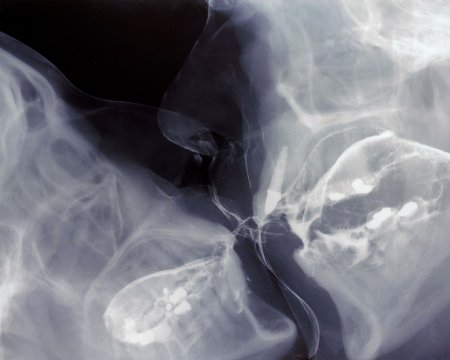

Рентгеновский эффект создает фантастические композиции в этих фотографиях девушки, чье тело становится прозрачным, демонстрируя скелет и внутренние органы. Она позирует в разных позах, ее силуэт светится загадочным свечением. Каждый кадр передает атмосферу научной фантастики и медицинского искусства. Ее кожа кажется полупрозрачной, позволяя увидеть кости и мышцы. Фотографии рассказывают о хрупкости человеческого тела и его внутренней красоте. Девушка то стоит в задумчивости, то делает грациозное движение. Эти иллюстрации вдохновляют на размышления о человеческой анатомии и уязвимости. Каждая картинка - это момент прозрения, когда внешнее уступает место внутреннему. Девушка воплощает образ современной Медузы, сочетающей красоту и загадочность.

Сквозь материю: тайны анатомии